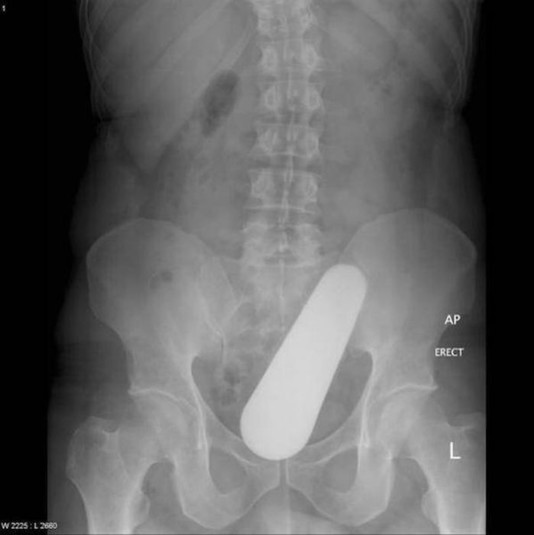

Предметы, которые не очень хочется видеть внутри себя

Под рентгеновскими лучами порой видны не только внутренние органы и кости, но и инородные тела, попавшие в организм

Истории попадания этих предметов в организм могут быть самыми невероятными и запутанными, но больше всего медиков интересует процесс их извлечения, впрочем, в этом заинтересованы и сами пациенты, допустившие нечто подобное со своим телом.